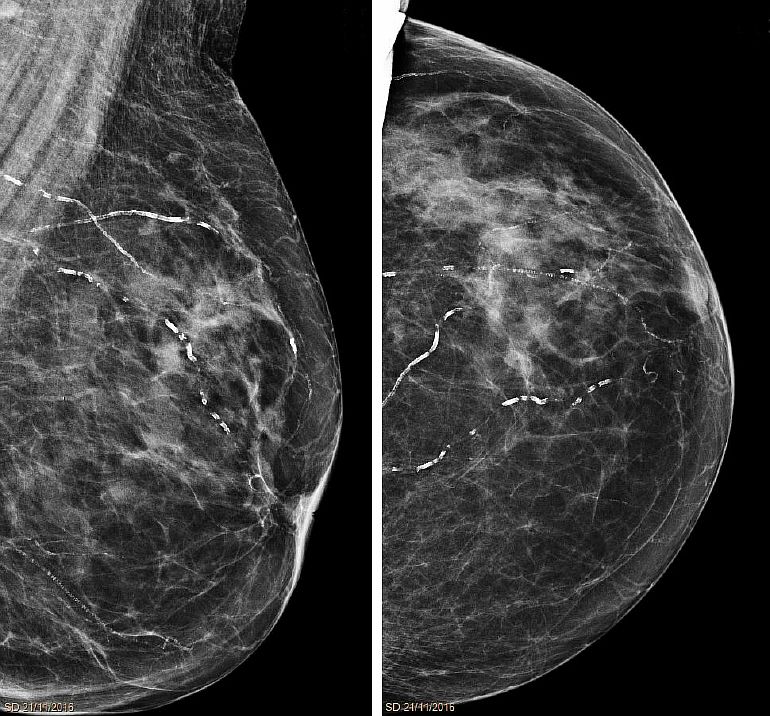

Выполняются два рентгеновских снимка груди, один спереди и один под наклоном, что позволяет сравнивать две стороны каждой груди.

Чтобы лучше изучить грудь, делаются несколько снимков или случаев (обычно по 2 на грудь) с разных точек зрения.

Результаты маммографии: классификация ACR

Маммография — это обследование, которое помогает врачу поставить диагноз. Система BIRADS Американского колледжа радиологии (ACR) используется для классификации маммографических изображений по 6 категориям.

- ACR 0: классификация ожидания, когда необходимы дальнейшие исследования.

- ACR 1: нормальная маммография.

- ACR 2: есть доброкачественные (то есть несерьезные) нарушения, которые не требуют мониторинга или дальнейшего обследования.

- ACR 3: вероятно, имеется доброкачественная аномалия, для которой рекомендуется .краткосрочный мониторинг (3 или 6 месяцев).

- ACR 4: имеется неопределенная или подозрительная аномалия.

- ACR 5: есть аномалия, указывающая на рак.

В случае изображений ACR 4 или ACR 5 требуются образцы для чрескожной биопсии.